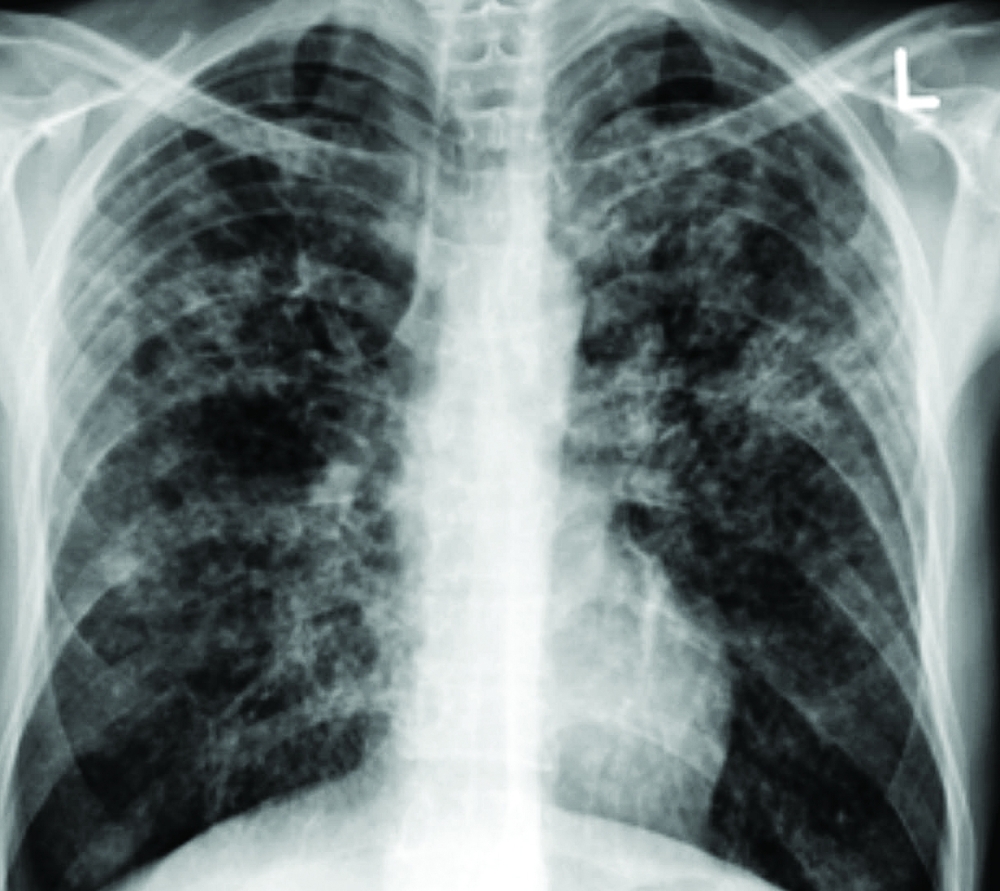

مشيرًا إلى أن معايير التشخيص تكمن في عدم وجود أعراض تنفسية لمرض السل النشط، وعادةً ما تكون صور الأشعة السينية للصدر طبيعية، بالإضافة إلى إيجابية فحص اختبار الـ"IGRA".

وأضاف: أن أشعة الصدر تعد إجراء أساسيًا للأشخاص الذين ثبتت إيجابية فحص الـ"IGRA"، وذلك للتأكد من عدم وجود آثار عدوى في الرئتين وهي خطوة مهمة للتأكد من عدم وجود السل النشط، كما يتطلب عمل فحص وظائف الكبد قبل البدء في علاج السل الكامن لمعرفة خلو الكبد من أي أمراض لمتابعة العلاج بعد ذلك.